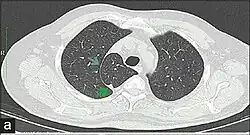

Azygos lobe

In human anatomy, an azygos lobe is a normal anatomical variation of the upper lobe of the right lung.[1] It is seen in 0.3% of the population.[2] Embryologically, it arises from an anomalous lateral course of the azygos vein,[3] in a pleural septum within the apical segment of the right upper lobe or in other words an azygos lobe is formed when the right posterior cardinal vein, one of the precursors of the azygos vein, fails to migrate over the apex of the lung and penetrates it instead, carrying along two pleural layers as the azygous fissure, that invaginates into the upper portion of the right upper lobe.[1]

An azygos lobe is usually an incidental finding on chest x-ray or CT scan. It is asymptomatic and not associated with any morbidity.[4][5] However, it can cause technical problems in thoracoscopic procedures.[6] The presence of the azygos lobe could alter the normal location of the superior vena cava or may be associated with other anomalies, including esophageal atresia or intrapulmonary right brachiocephalic veins.[7]